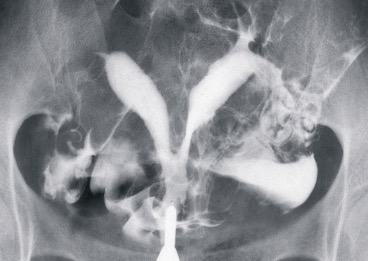

5) Anormal Histerosalpingografi (HSG) ve Ultrason bulgularının kesinleştirilmesi için :

Yapılan HSG veya USG tetkiklerinde rahimde şekil bozuklukları ve rahim içinde polip, myom, yapışıklık gibi

durumları düşündüren görüntülerin kesinleştirilmesi için histeroskopi yapılabilir.